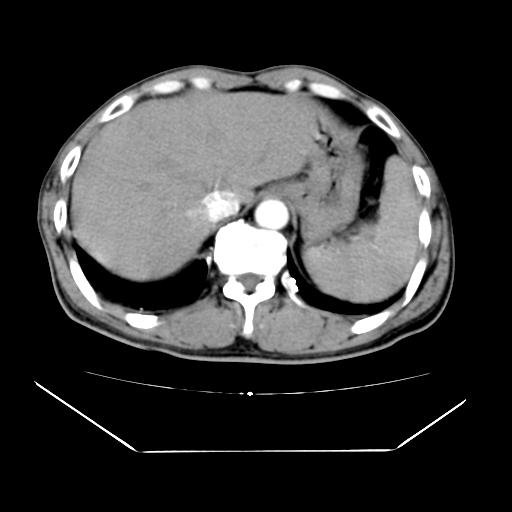

男性,55岁,外院体检afp明显升高,但b超未发现异常,否认乙肝病史。来我院ct增强。有延时扫描。

延时扫描完全充填,血管瘤

肝脏右叶动脉期可见低密度影,至延迟期被充填,考虑血管瘤可能性大。

肝右叶病灶

不排除肝右叶肝癌可能。

肝6段血管瘤

血管瘤可能性大。

考虑肝右静脉影。